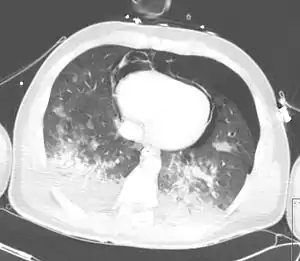

Computed tomography

Computed tomography (CT scanning) is a more sensitive test for pulmonary contusion,[6][33] and it can identify abdominal, chest, or other injuries that accompany the contusion.[38] In one study, chest X-ray detected pulmonary contusions in 16.3% of people with serious blunt trauma, while CT detected them in 31.2% of the same people.[45] Unlike X-ray, CT scanning can detect the contusion almost immediately after the injury.[43] However, in both X-ray and CT a contusion may become more visible over the first 24–48 hours after trauma as bleeding and edema into lung tissues progress.[46] CT scanning also helps determine the size of a contusion, which is useful in determining whether a patient needs mechanical ventilation; a larger volume of contused lung on CT scan is associated with an increased likelihood that ventilation will be needed.[43] CT scans also help differentiate between contusion and pulmonary hematoma, which may be difficult to tell apart otherwise.[47] However, pulmonary contusions that are visible on CT but not chest X-ray are usually not severe enough to affect outcome or treatment.[37]